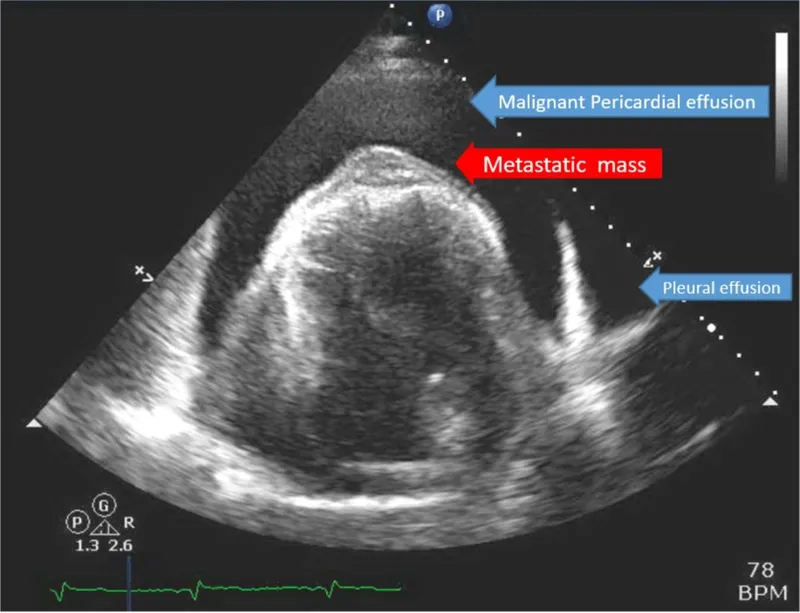

Metastatic Cardiac Tumors - Secondary Spread

- Significantly more common than primary cardiac tumors, occurring 20-40 times more frequently.

- Most frequent primary origins:

- Lung carcinoma (often by direct extension)

- Breast carcinoma

- Malignant melanoma (high cardiac tropism)

- Leukemia and lymphoma

- Pericardium is the most common site, followed by myocardium, then endocardium.

⭐ Malignant melanoma has the highest relative incidence of cardiac metastasis among all tumor types.

- Echocardiography (TTE/TEE): First-line; identifies mass, location, mobility.